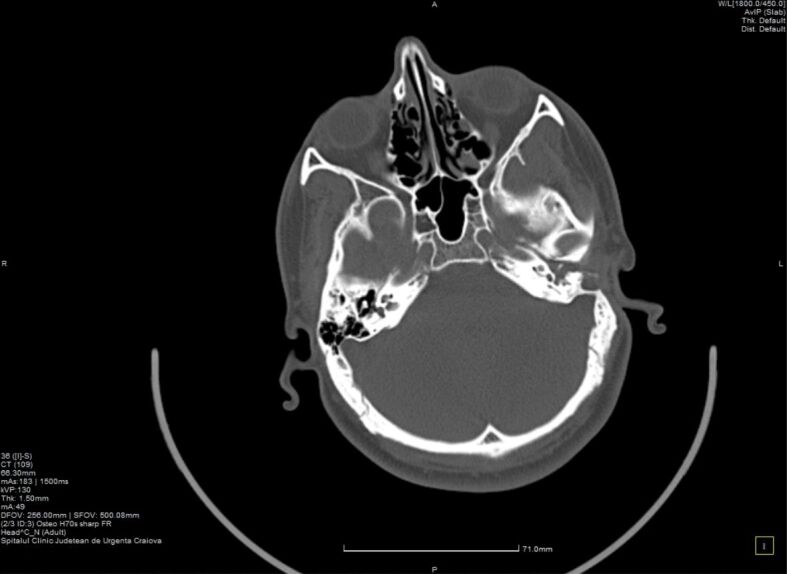

胆脂瘤是一种耳科病变,可发生于任何年龄,并可导致各种并发症,包括面瘫、颅内脓肿、听力损失、静脉血栓形成等。胆脂瘤即使被认为是一种良性疾病,但由于其侵袭性,复发的风险也很高。我们描述了一例复发性胆脂瘤病例,患者为一名年轻男孩,在 16 岁至 19 岁(2019 年至 2022 年)期间,曾因慢性耳流脓和听力下降接受过三次手术治疗。小儿胆脂瘤更容易复发。考虑到手术切除是目前唯一的治疗方法,了解胆脂瘤病变扩展的生物学特性对于进一步改善治疗管理非常重要。对与手术方法相关的血管生成、慢性炎症和免疫浸润进行深入研究可能是预防胆脂瘤复发的未来方向。

Cholesteatoma is an otologic pathology that can occur at any age and can lead to a variety of complications including facial palsy, intracranial abscess, hearing loss, venous thrombosis. Cholesteatoma, even if considered a benign condition, associates high risks of recurrency due to its invasiveness. We describe a case of recurrent cholesteatoma in a young boy who presented chronic ear discharge and hearing loss for which had undergone three surgical interventions between the ages of 16 and 19 years old, from 2019 to 2022. Pediatric cholesteatoma is more prone to recurrency. Considering surgical excision as the only treatment at the current moment, it is highly important to understand the biology of cholesteatoma lesional extension for further treatment management improvement. Good research of angiogenesis, chronic inflammation and immune infiltration correlated with surgical approach may be the future for preventing cholesteatoma recurrency.